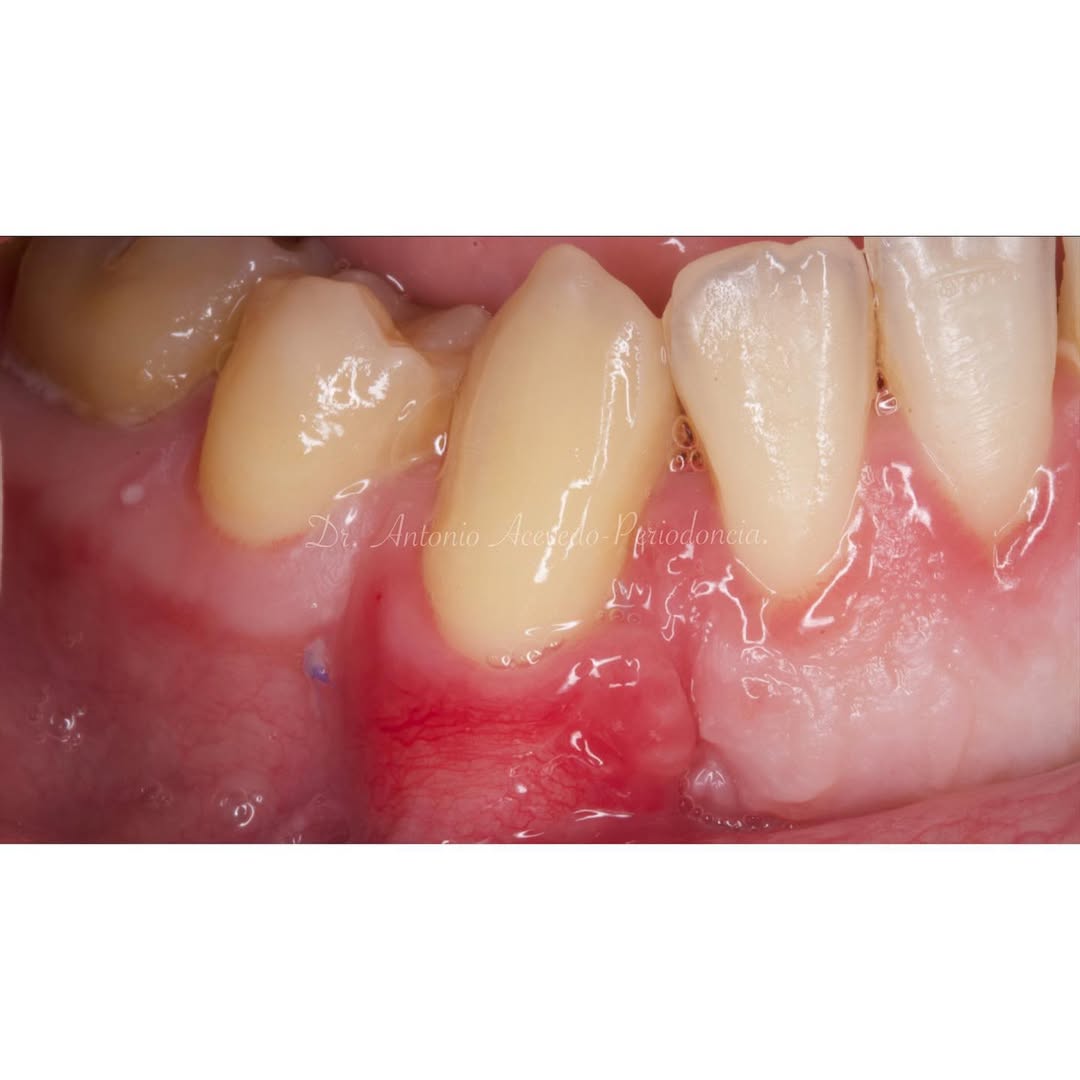

Aprende la planificación y técnica de la cirugía Mucogingival para el recubrimiento de recesiones y aumento de banda queratinizada en el sector anteroinferior

Durante una mañana, asistirás a una Cirugía Mucogingival de recubrimiento radicular de recesiones múltiples en IV y V sextante (36 a 43).

La formación comenzará con la presentación del caso clínico que se abordará durante el curso, seguida de una cirugía en directo, que permitirá observar paso a paso el procedimiento y la toma de decisiones clínicas. Durante la jornada se profundizará en los conceptos biológicos aplicados a